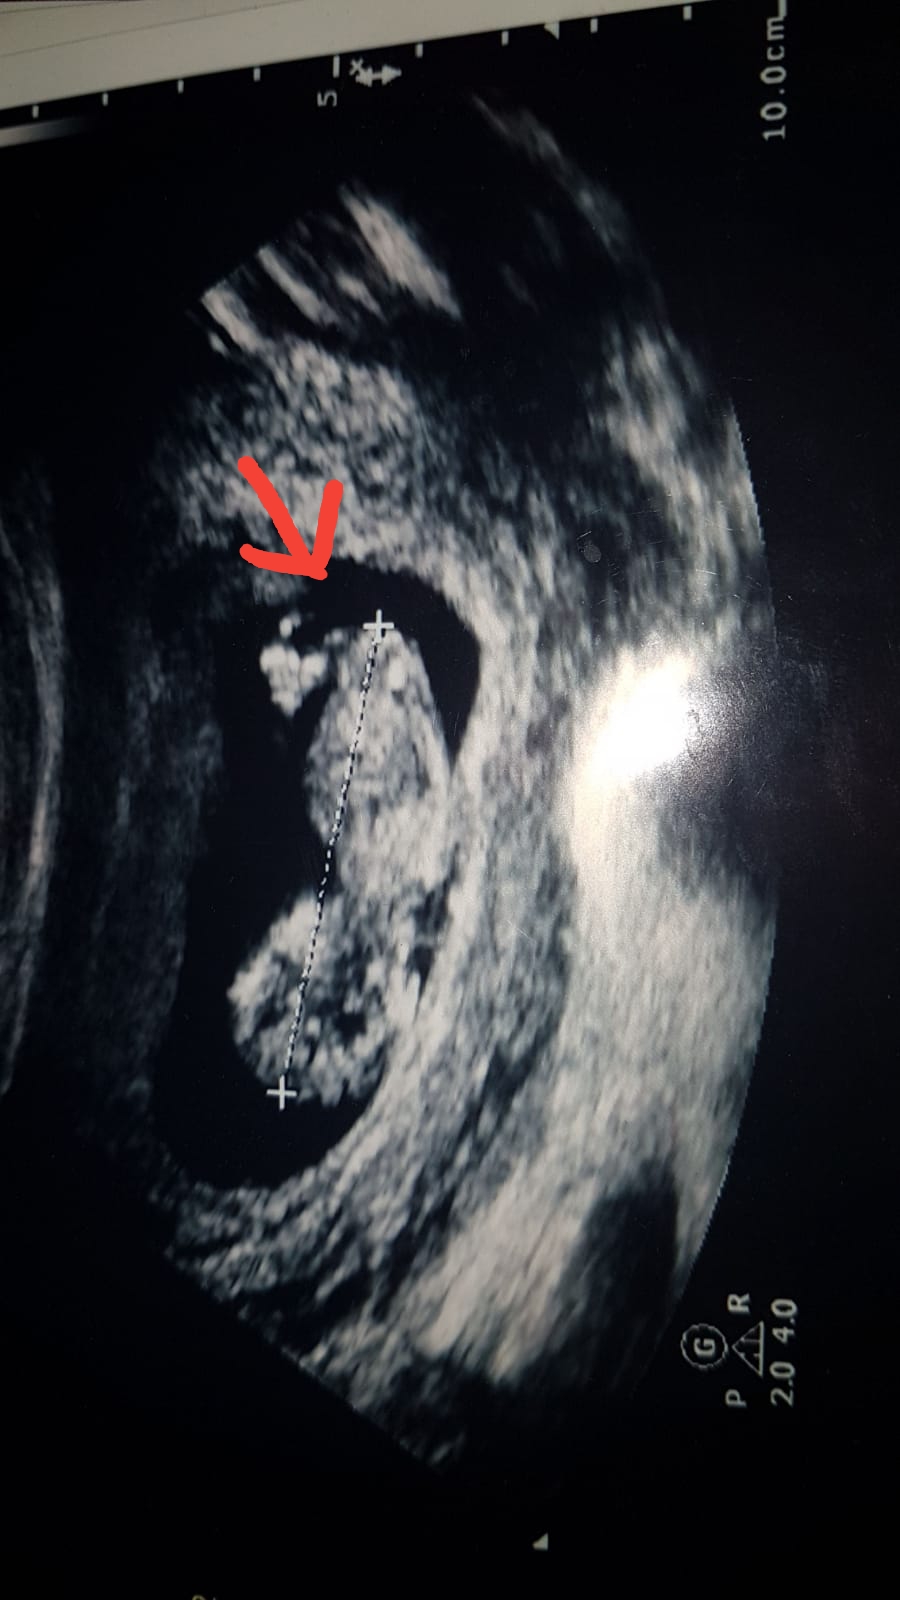

merhaba bu bebegimin 12 haftalik resmi doktor bu haftada erkek dedi suan 18 haftaligiz ve bir baska doktor 18 haftalikken ultrasonda bebek bagdas kurmus bacaklarini acmiyor kiz olabilir dedi simdi kafam karisti 12 haftalikken ki ultrason resmindeki bacak arasindaki cikinti ne anlama geliyor lutfen yorumlarmisiniz

aslinda merak ettigim su okla gosterdigim yer.12 haftalik bebegin genital organlari bu haftada tam olusmus olabilir mi ve ultrasonda bu kadar net gorulebilir mi ki doktorum cok net bir sekilde erkek demisti

Bebeğin cinsiyeti oluştuğu andan itibaren bellidir aslında ama bu en erken nub teoirisi ile 12. haftada öğrenilebilir. Bu haftalarda yanılma payı yüksektir bu nedenle benzer paylaşımların hepsine bebeğin cinsiyetinin 17-19-20 haftalarda net şekilde öğrenilebileceği notunu düşüyoruz.